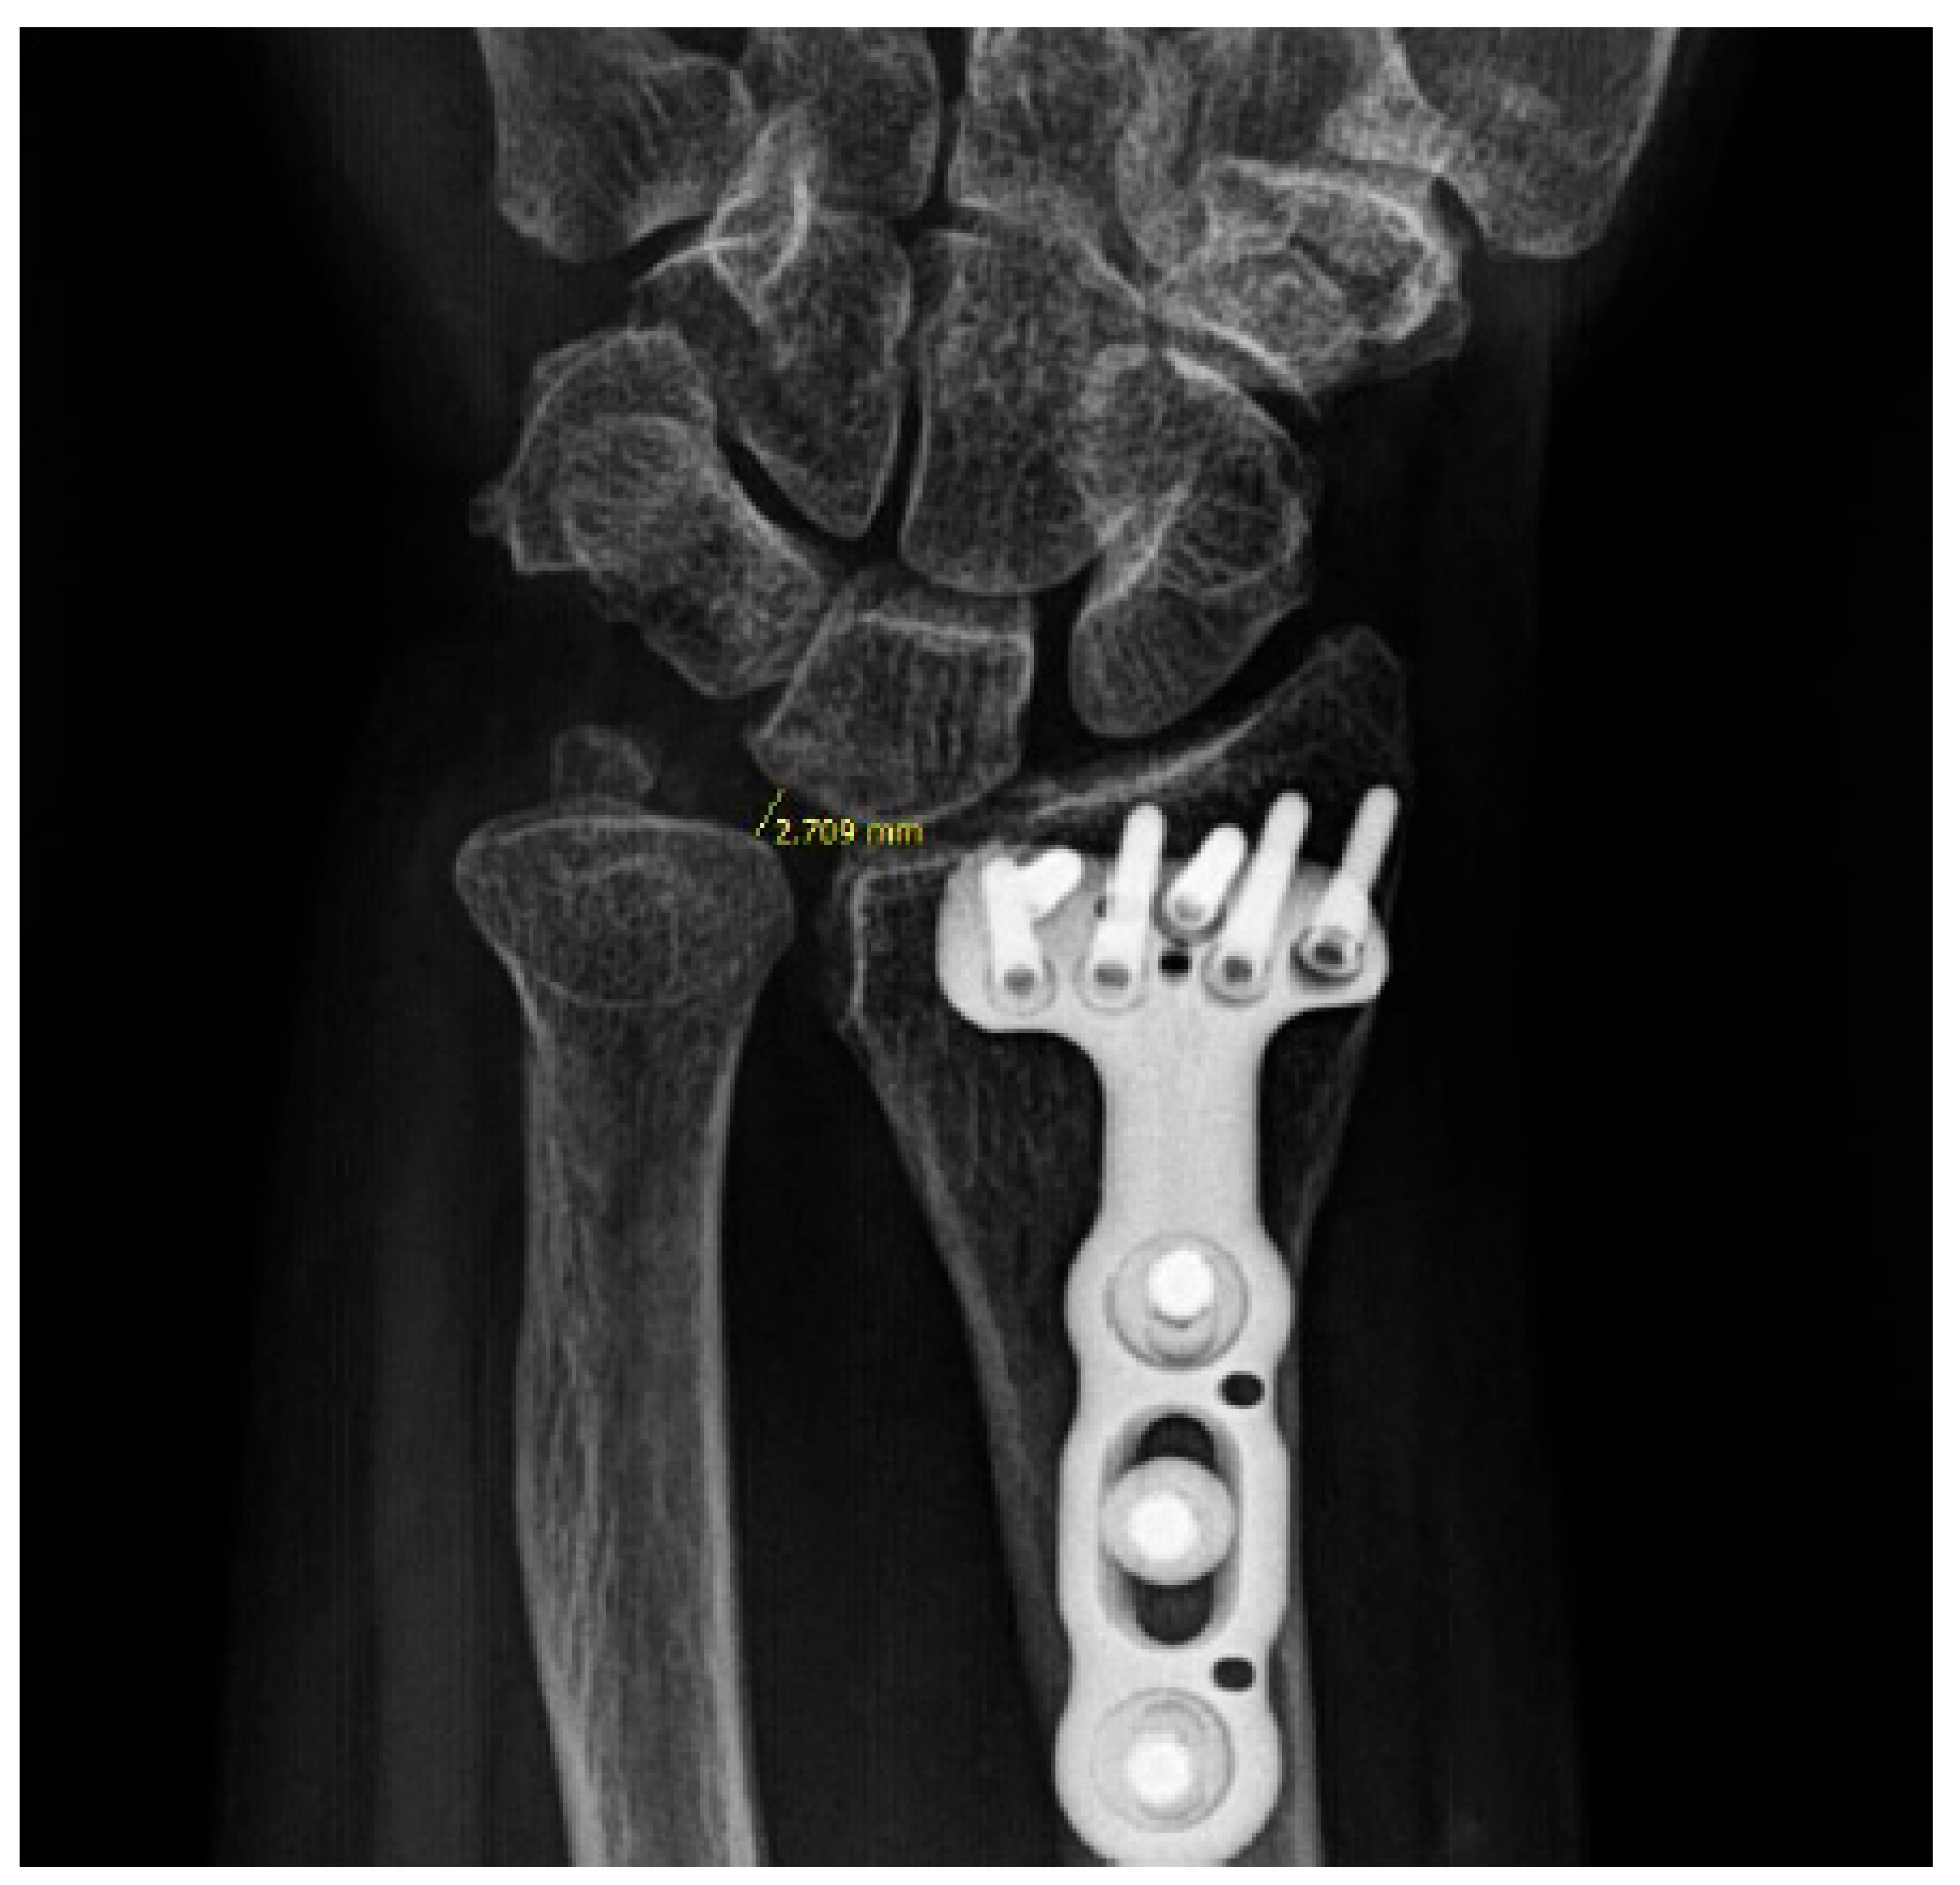

Radiologic Evaluation: Radiologic parameters, specifically ulnar variance and ulnolunate distance, were measured immediately postoperatively and at the final follow-up. Measurements were performed twice by two orthopaedic residents independently, and the mean values were used for analysis. Ulnar variance was measured on standard PA wrist radiographs (taken with the shoulder abducted 90°, elbow flexed 90°, and forearm in neutral rotation) using the method of perpendiculars. To compensate for potential measurement errors in ulnar variance, we also measured the ulnolunate distance, defined as the shortest distance between the lunate ulnar corner and the most convex point of the ulnar head (Figure 1 and Figure 2). Additionally, the location of the lunate cyst was evaluated using preoperative computed tomography (CT). Preoperative CT was obtained as part of routine clinical care when intra-articular involvement or complex fracture morphology required further assessment for surgical planning, and it was not performed solely for research purposes. CT acquisition followed our institutional clinical protocol, and no additional imaging was requested specifically for this retrospective study. Cysts were classified as dorsal or palmar based on sagittal CT images. Cysts that could not be clearly localized to either side were categorized as “unclassified” (Figure 3).

Figure 2. Measurement of ulnolunate distance.

Surgeries 07 00039 g002